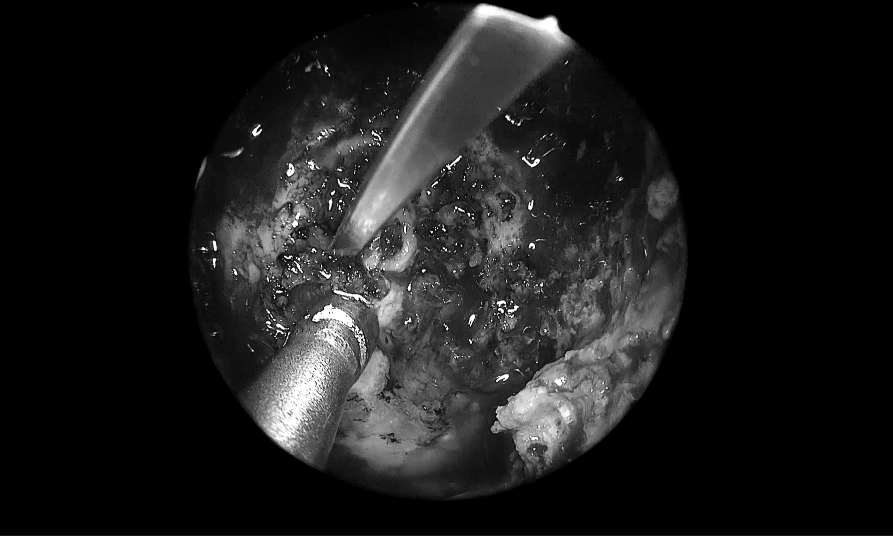

▼INC福教授术中操作步骤图解

术中操作步骤图解

▼单鼻孔进入,粘膜切开

取出部分肿瘤,进行瘤内减压